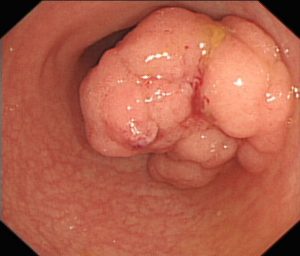

Ο πολύποδας είναι μία μάζα κυττάρων,ένα μικρό εξόγκωμα, της εσωτερικής επένδυσης του παχέος εντέρου .Ένας πολύποδας σε σχέση με την εσωτερική επιφάνεια του εντέρου μπορεί να είναι επίπεδος ή ανυψωμένος. Υπάρχουν διάφοροι τύποι πολυπόδων, και μερικοί μπορούν τελικά να αναπτυχθούν με την πάροδο του χρόνου και να γίνουν καρκίνος.

Κολονοσκόπηση: Μια διαδικασία κατά την οποία ένας μακρύς, λεπτός, εύκαμπτος σωλήνας τοποθετείται από τον πρωκτό μέσα στο παχύ έντερο. Ο σωλήνας διαθέτει μια κάμερα που δείχνει εικόνες σε μια οθόνη και ένα εργαλείο για να κόψει τυχόν πολύποδες.

Όταν εντοπιστεί ένας πολύποδας, ο γιατρός θα το αφαιρέσει και θα το εξετάσει για να δει τι είδους είναι. Οι περισσότεροι πολύποδες αφαιρούνται κατά τη διάρκεια μιας κολονοσκόπησης. Ο γιατρός σας θα καθορίσει πότε θα πρέπει να πραγματοποιήσετε μια επανάληψη της εξέτασης ελέγχου βάσει του αριθμού των πολύποδων, του τύπου των πολύποδων και των παραγόντων κινδύνου.